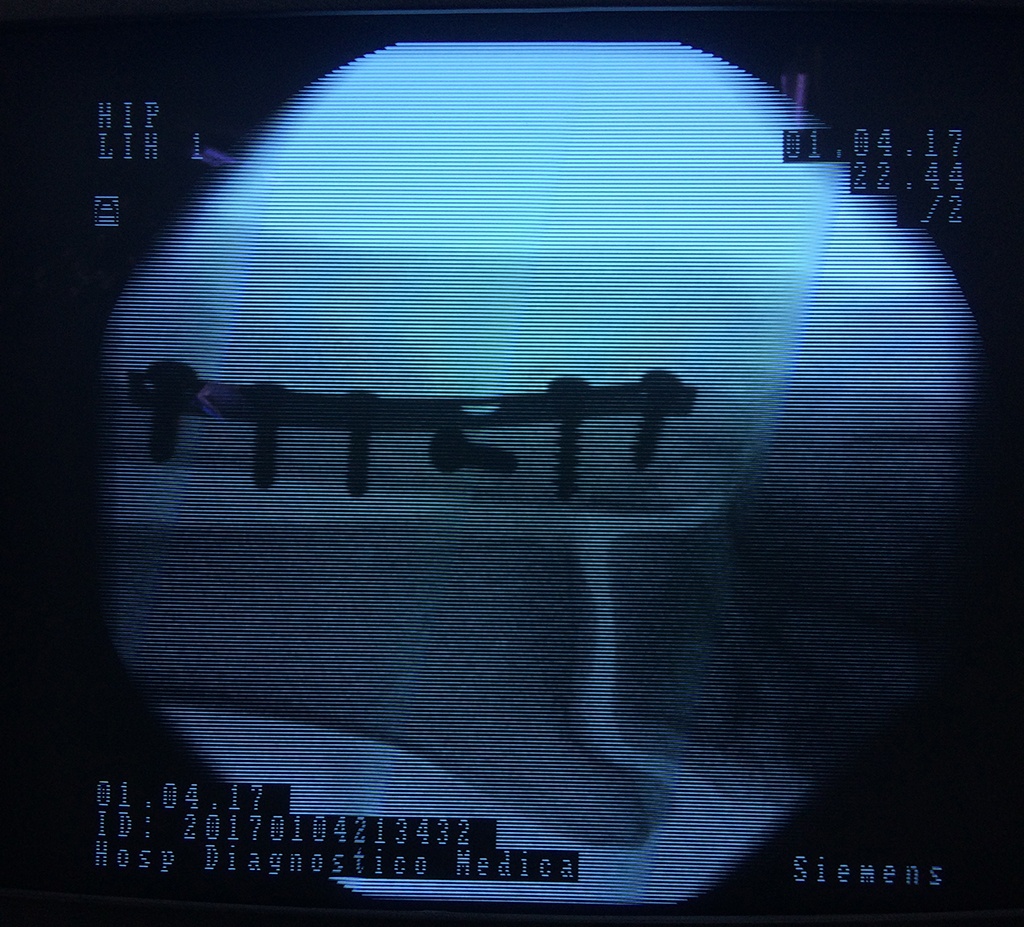

Cuando se necesita cirugía, es probable que esta implique el uso de clavijas de metal, tornillos o placas para sostener los huesos en su lugar mientras la fractura se consolida. Los elementos de soporte pueden ser temporales o permanentes.

Cirugía de Tobi...

Detail Download